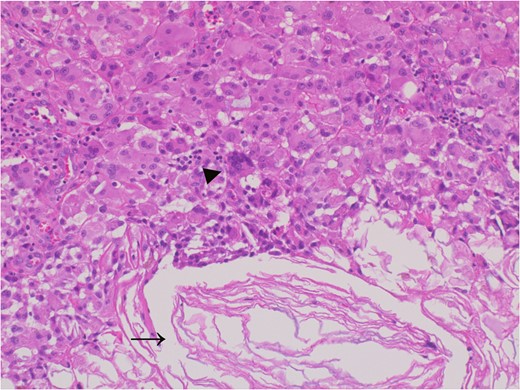

The adhesive region revealed keratin (allow) which flowed outside the cyst and granulomatous response for keratin with multinucleated giant cells (allow head), Hematoxylin and eosin stain, ×20 magnification.